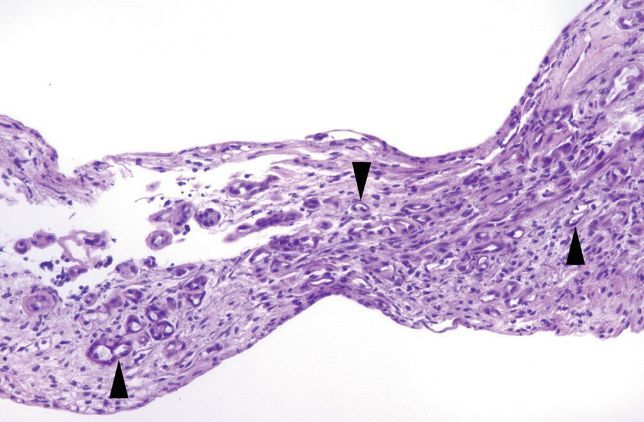

Invasive urothelial carcinoma, or “the tumor formerly known as ‘transitional cell carcinoma’”

Most arise within the setting of either high-grade papillary urothelial carcinoma or flat carcinoma in-situ.

Characterized by irregular tongues of cells or single cells pushing into the lamina propria. “Paradoxical differentiaton” is often present. A retraction artifact separating the stroma from tumor nests is present in H&E preparations. There may or may not be a desmoplastic response.

Paradoxical differentiation

Seen in invasive urothelial carcinoma/transitional cell carcinoma

The deep invasive cells acquire increased pink cytoplasm, mimicking mature surface cells.